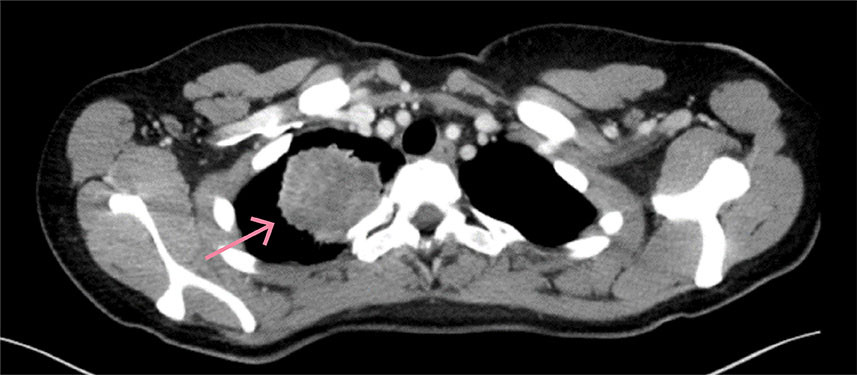

CT- og MR-undersøkelser av hodet avdekket en 23 mm stor ekspansiv prosess med omgivende ødem i venstre talamus som utøvet masseffekt på tilstøtende venstre sideventrikkel (figur 1a–d). CT-undersøkelse av brysthulen avdekket en 5,6 cm stor svulst i høyre lunges overlapp (figur 2). Det forelå forstørrede lymfeknuter paratrakealt på høyre side (stasjon 4R) og paraaortalt (stasjon 6R).

Man mistenkte nå lungekreft med spredning til lymfeknuter og hjerne. Finnålsaspirasjonscytologi etter bronkoskopisk prøvetaking fra lymfeknute 4R viste metastase fra lavt differensiert ikke-småcellet karsinom og bekreftet diagnosen.